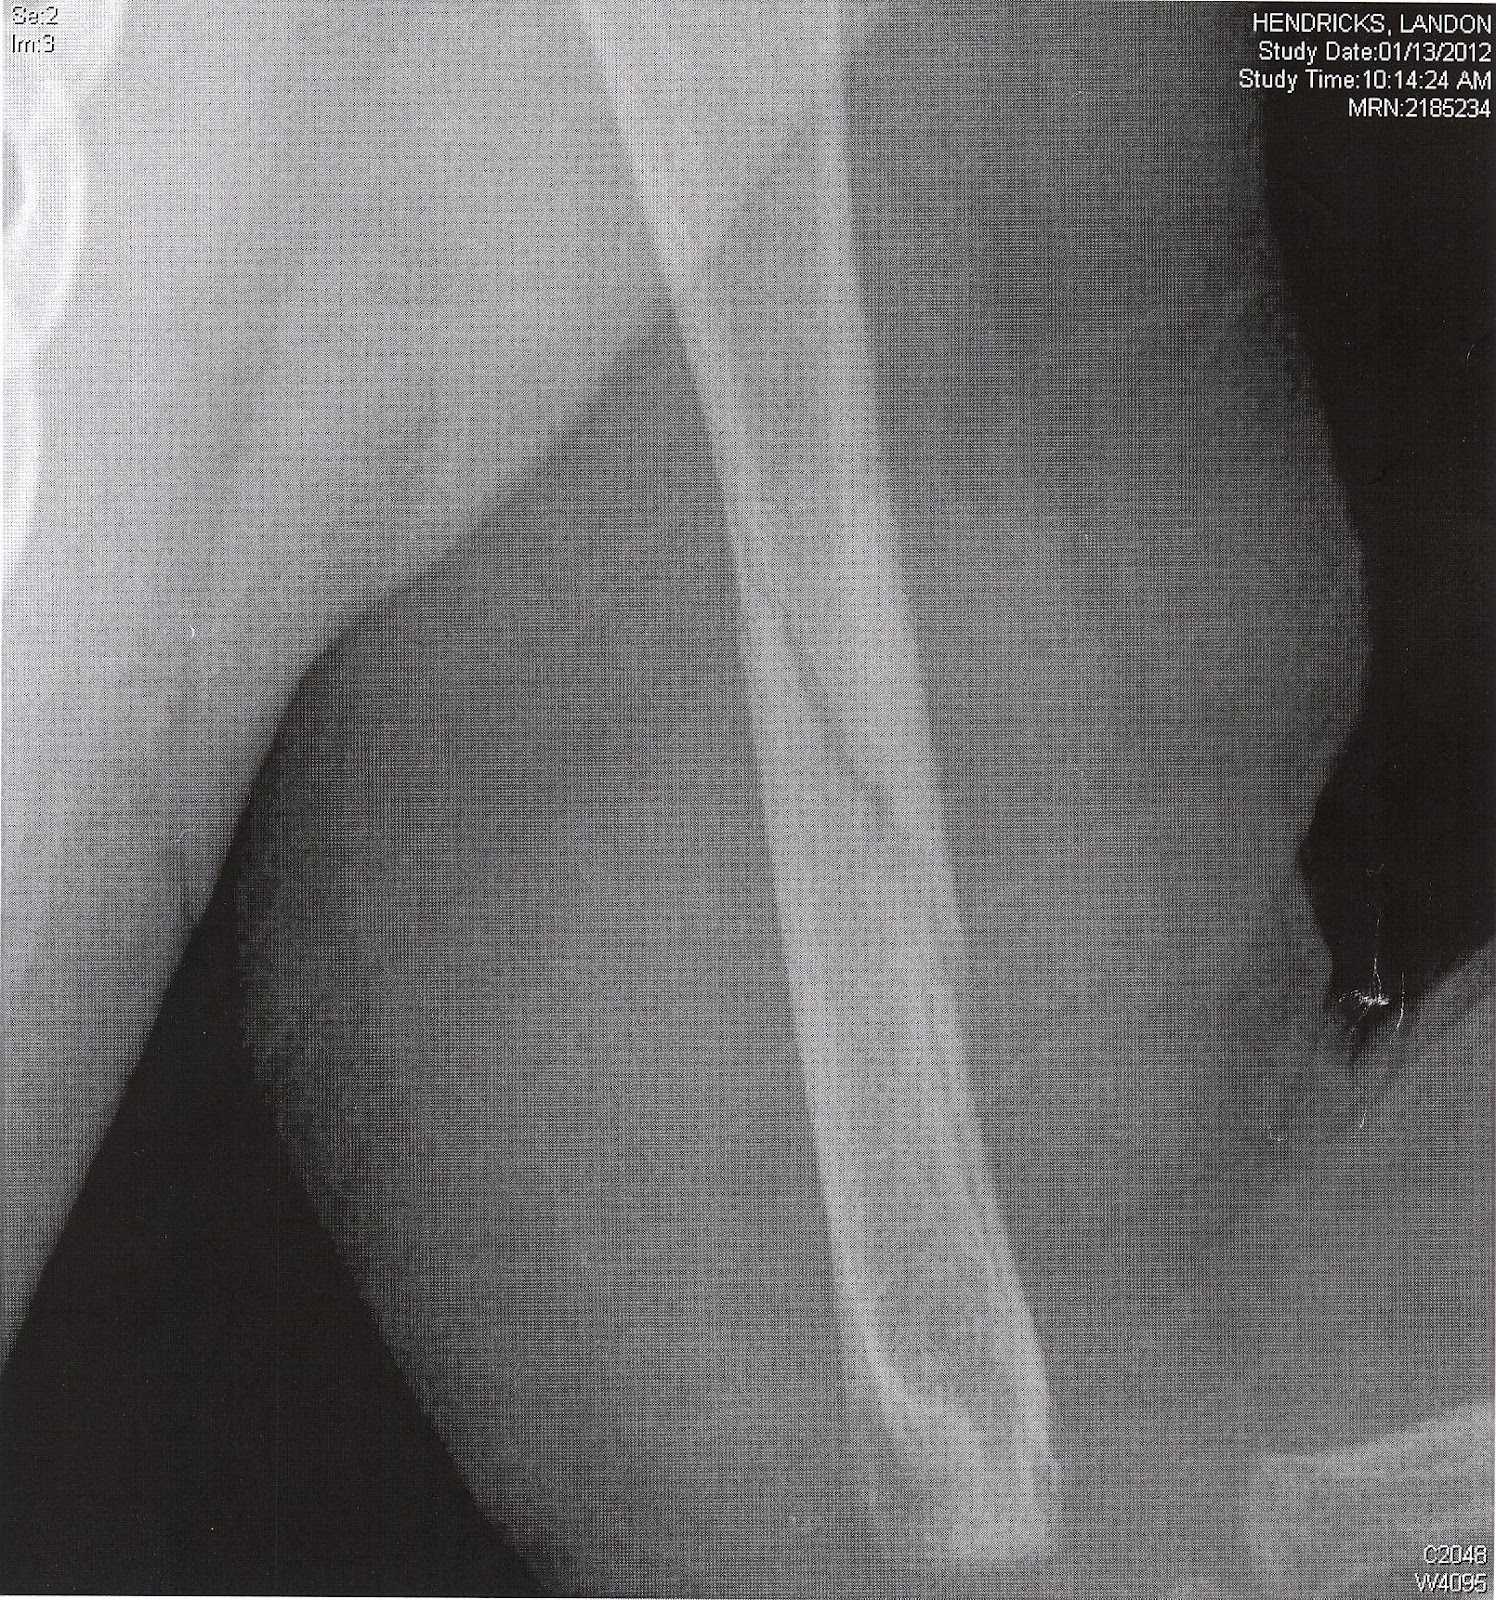

January was a bad month for my little guy :(. I laid Landon down on the floor for a minute while i went into the other room to get something. I had just told the girls not to touch him, like i do 50 times a day. I left his sight for 10 seconds when i heard him scream and start crying. Right away i knew exactly what happened. Ashley just couldn't resist trying to play with him. He had just learned how to roll around and Ashley thought she would help him out. She didn't realize his arm was pinned back and just kept pushing him until his arm broke. I think i cried as much as he did that day. There is nothing worse than seeing your baby in pain. For about a month we had the challenge of trying to immobilize his arm. At first we tried the ace bandage but then resorted to safety pinning his arm to his chest. It drove him crazy not being able to move his arm or roll around anymore but at least he never seemed to be in any pain. We just got another x-ray taken last Friday and it is healing great. You can still see the break but at least he is able to use his arm now.